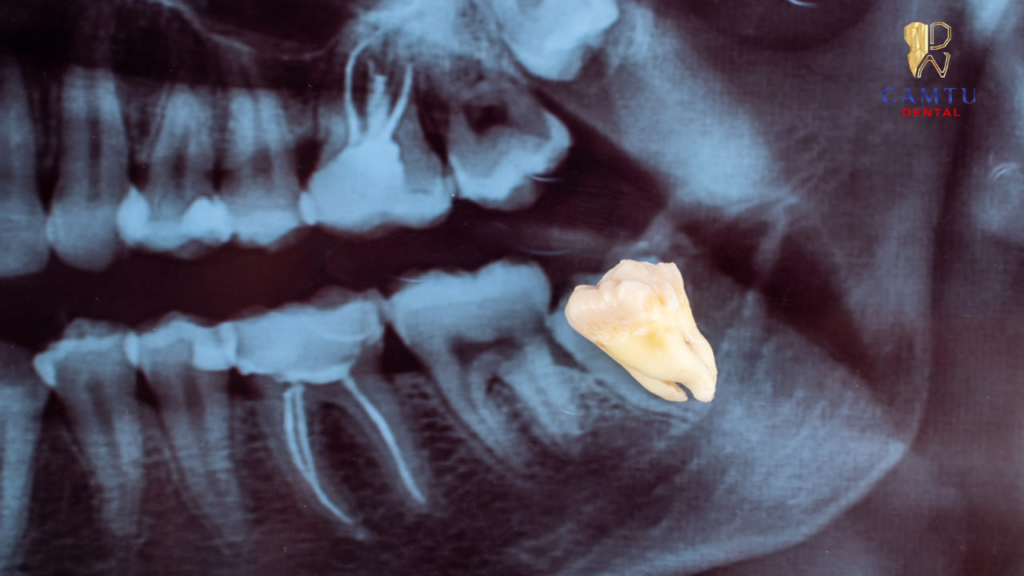

Thăm khám và chụp X quang răng

Bác sĩ tiến hành kiểm tra tổng quát khoang miệng để đánh giá tình trạng răng khôn, sau đó chỉ định chụp X quang răng. Hình ảnh X quang giúp xác định chính xác vị trí răng số 8, hướng mọc, độ nghiêng cũng như mối liên quan với các răng lân cận, từ đó đưa ra phương án nhổ răng phù hợp và an toàn.

Trong một số trường hợp răng số 8 mọc gần dây thần kinh hàm dưới, việc nhổ răng cần được thực hiện cẩn thận. Tuy nhiên với chẩn đoán X quang chính xác và kỹ thuật của bác sĩ, nguy cơ ảnh hưởng đến dây thần kinh là rất thấp.